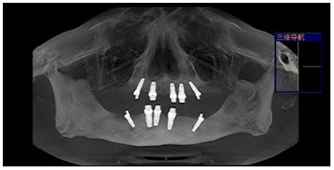

宁德中富口腔种植科医生对李大爷的口腔情况进行系统检查后,诊断李大爷为重度牙周病导致全口牙齿缺失。由于李大爷牙齿缺失时间较长,导致牙槽骨严重萎缩,故拟定人工植骨后三个月,采用微创口腔种植。

人工植骨三个月后,骨量达到种植标准。主治医生在上下颌共植入8颗种植体。医生为李大爷取模,制作临时牙。